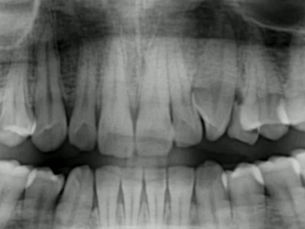

At Jehangir Oracare Dental Centre, our Advanced 2D & 3D CBCT Dental Scan allows dentists to see your teeth, nerves, jawbone and surrounding structures in high-definition 3D helping detect problems early and plan treatments with precision. ✔ See teeth, nerves & bone in 3D ✔ Accurate diagnosis for implants, root canals & surgeries ✔ Quick, safe & painless scan ✔ Advanced CBCT technology available at our clinic Because the right treatment begins with the right diagnosis Book you